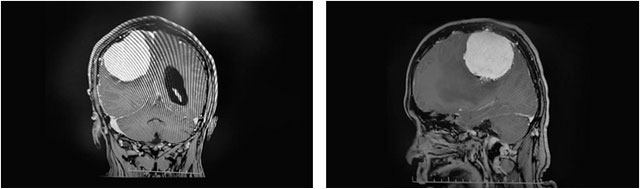

患者頭顱MRI提示,右側(cè)頂部大腦凸面可見一團(tuán)塊狀異常信號影,邊緣清晰,輪廓光整,大小約為6.1×5.7×5.1cm,體積巨大,形同鵝蛋狀;毗鄰額頂葉、基底節(jié)區(qū)見片狀長T1、長T2水腫信號影,鄰近腦組織受壓移位變形,右側(cè)側(cè)腦室受莊變窄,中線結(jié)構(gòu)向左側(cè)偏移。

▲ 腫瘤位于右側(cè)頂葉部

李士其教授介紹,杜先生腦中的這顆腦膜瘤位于右側(cè)頂葉部,大腦的運(yùn)動功能區(qū)內(nèi),對肢體神經(jīng)造成了壓迫,這也是導(dǎo)致杜先生左手手指麻木、無力,左側(cè)大腿麻木的主要原因。而且由于拖延一年沒有盡早手術(shù)治療,腫瘤已經(jīng)長到鵝蛋般大小,直徑約達(dá)6公分。“患者的這顆腫瘤體積很大,對周邊的運(yùn)動功能區(qū)神經(jīng)造成嚴(yán)重壓迫,隨時都有讓患者癱瘓的可能,也為手術(shù)操作帶來巨大挑戰(zhàn)。而且腫瘤與大血管粘連,血供極其豐富,手術(shù)中一旦有絲毫差錯,都有可能造成術(shù)中大量出血,直接威脅到患者的生命安全。”